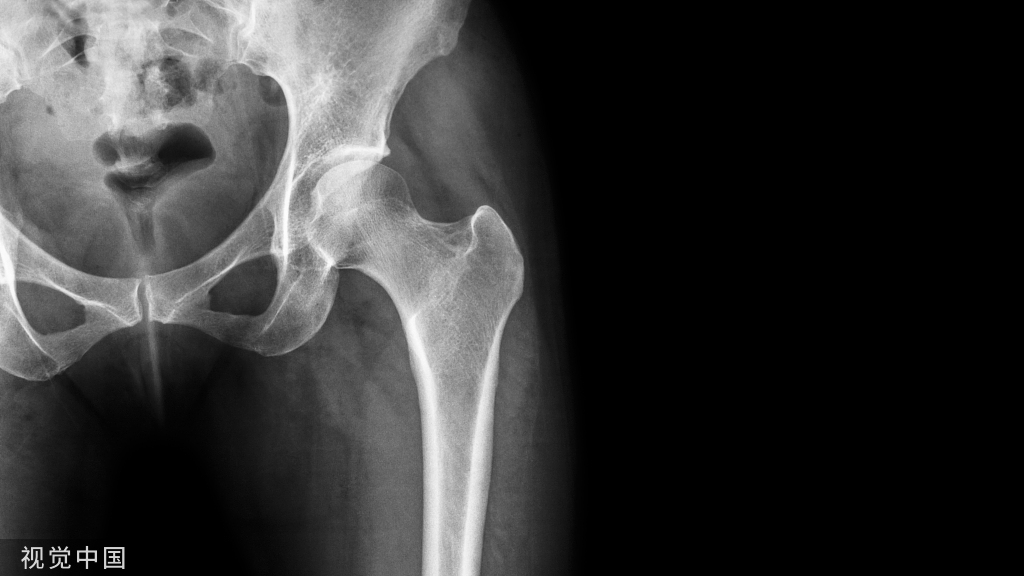

髋关节骨性关节炎的确诊首先需要依据 X 线平片上髋关节表现,包括关节间隙变窄、软骨下骨硬化和囊性变,关节边缘增生和骨赘形成等。